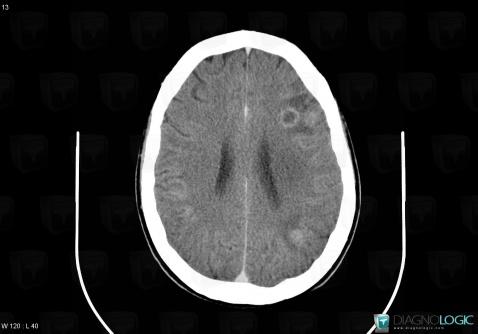

Toxoplasmosis, Cerebral hemispheres, CT

Here is the specific information in the key image above:

- Diagnosis Toxoplasmosis (link to Abscess), Location(s) Cerebral hemispheres, with gamuts Intracerebral lesion with ring enhancement, Intracerebral lesion with moderate enhancement, Multifocal intracranial lesions